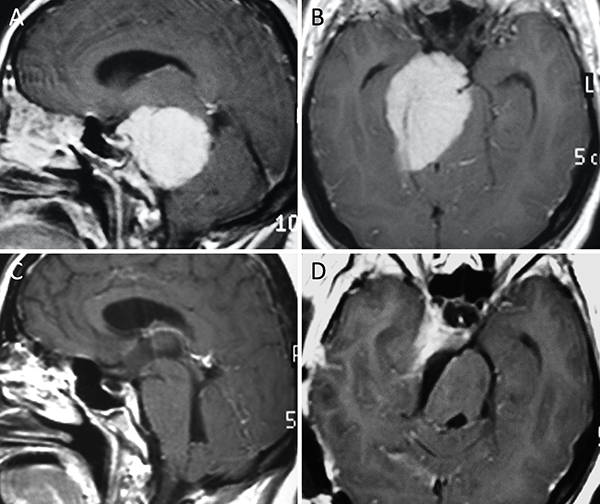

Figura 11. Meningioma del foramen magno posterior. A-B: RM preoperatoria; C-D: RM postoperatoria.